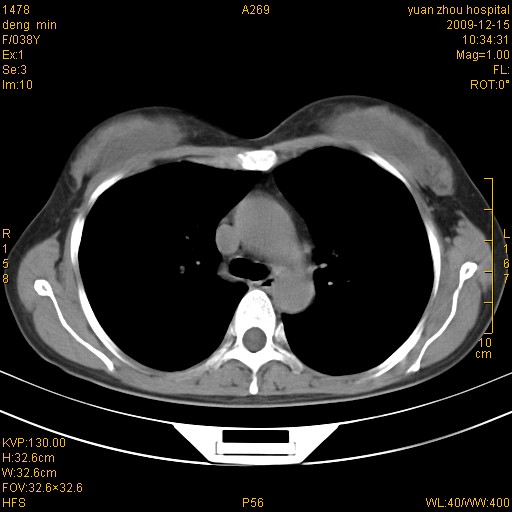

标题: CT23919:F38Y 咳嗽月余 [打印本页]

标题: CT23919:F38Y 咳嗽月余

右肺中下叶、左肺上叶舌段及左肺下叶支气管扩张合并感染。